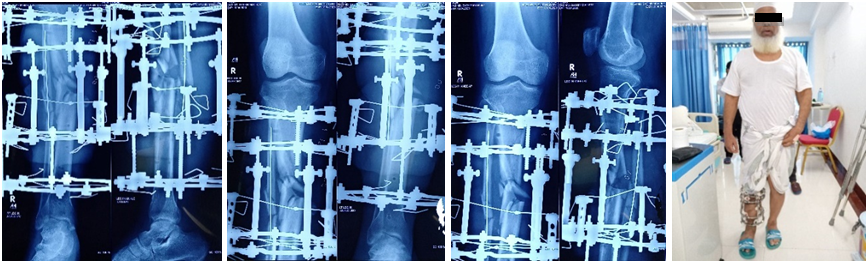

After 7 weeks of trauma and flap covering surgery the Ilizarov osteosynthetic device was applied as a definitive management. A four ring Ilizarov was set with one separate olive extractor for loss fragment to turn it to place (Figure 4). The patient walked with full weight bearing on both feet without any support on very 1st post operative day of Ilizarov ring fixation.

During the evaluation of the outcome the ASAMI criterion was used to evaluate the final results. An excellent result was defined as fracture union with full knee extension and more than 125° flexion, ankle range of motion >75% of normal, limb length discrepancy <2.5 cm, no angulation >7° in any plane, no rotation >7° and absence of infection. According to ASAMI criterion the functional outcome was excellent (Figure 5).